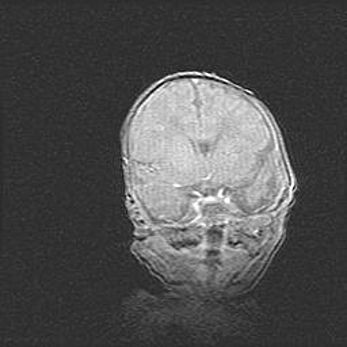

Наружная гидроцефалия с возможной атрофией височных областей.

Возраст: 28 дней

Вес: 3670 г

Пол: мужской

Окружность головы: 38 см

Срок гестации: 40 недель

Гидроцефалия головного мозга у новорожденных – это заболевание, которое характеризуется скоплением избыточного количества спинномозговой жидкости в желудочковой системе головного мозга в результате затруднения её перемещения от места выработки к месту поглощения в кровеносную систему или вследствие нарушения абсорбции. При открытой наружной форме гидроцефалии у новорожденных расширяются и переполняются субарахноидные пространства.

При нормотензивных  формах,  которые,  как  правило,  являются  следствием  перенесенных ишемических  повреждений  паренхимы  мозга,  возможно  сочетание микроцефалии  с нормотензивной гидроцефалией. В основе данных изменений лежит атрофия больших полушарий с преимущественной  локализацией  в  лобно-височных  областях.